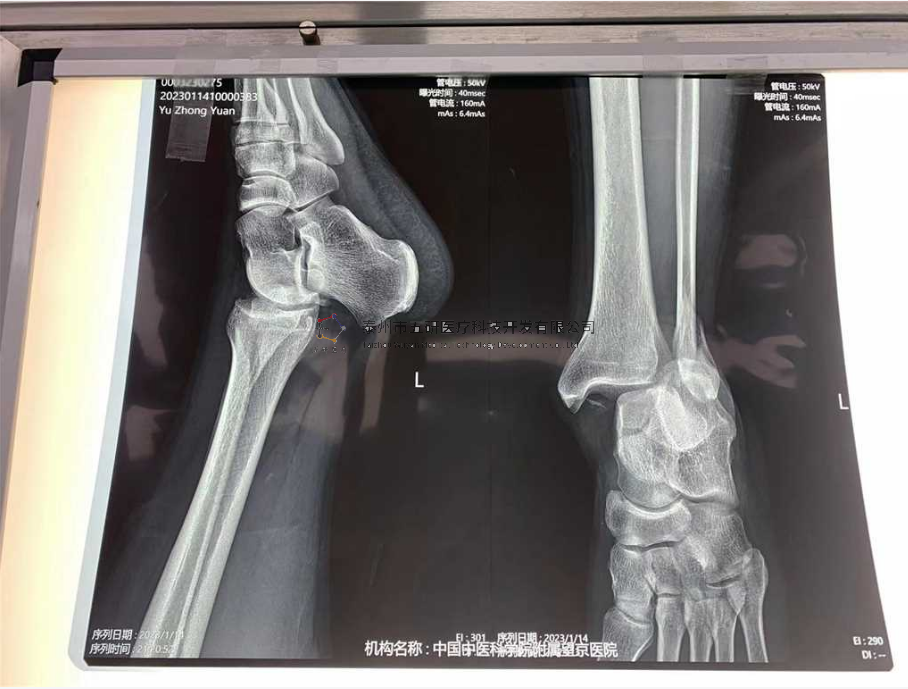

本病例踝關(guān)節(jié)骨折。手術(shù)名稱:左踝關(guān)節(jié)骨折外固定支架手術(shù)

【治療前影像】

4.png